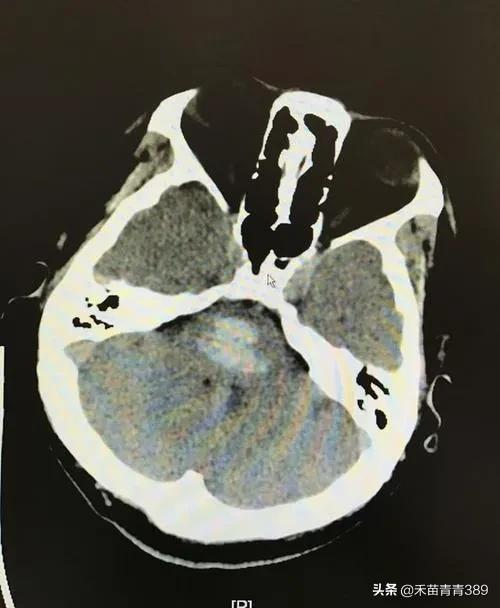

2022-09-22 01:43 阅读: 评论:脑出血是指原发性非外伤性脑实质出血,占急性脑血管病的20%~30%,约80%的出血部位发生在大脑半球,约20%的出血发生在脑干和小脑,发病年龄多在50岁以上,根据出血部位不同可分为,基底节区出血,丘脑出血,脑叶出血,脑干出血,小脑出血和脑室出血七种。根据病因不同,可分为原发性脑出血和继发性脑出血。根据出血量多少不同,临床症状轻重不同,严重者可昏迷,危及生命,一般脑出血症状表现有头疼,头晕,恶心,呕吐,言语不利,视物模糊,肢体活动障碍,意识改变,出现上述症状高度怀疑脑出血,尤其是平时血压高,和年龄大的患者,需要迅速到医院就诊,进行脑CT检查,当确诊脑出血后,立即住院治疗,住院后常规给予稳定血压,脑脱水降低颅内压和相关治疗。比较严重的脑出血是脑干出血,脑室出血,和出血量大患者,

死亡率比较高,大部分脑出血患者在内科药物保守治疗,出血量比较大的脑出血,脑室出血,需要外科开颅手术,或者颅穿引流,降低颅内压,防止脑疝形成。脑出血预后,与出血部位,出血量多少以及是否有合并症相关。一般急性期七天,两周后病情逐步稳定,经过积极治疗,绝大部分患者可以好转出院。脑出血康复和预防,要特别注意血压,控制血压在正常水平,要戒烟戒酒,清淡饮食,避免劳累,控制体重,规律休息,适当运动,稳定血糖血脂。